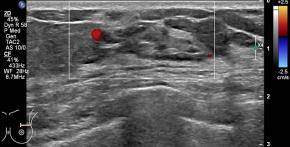

[355,Breast] 61/F,A palpable mass in the left breast

Breast

US,Etc,

What is your diagnosis?